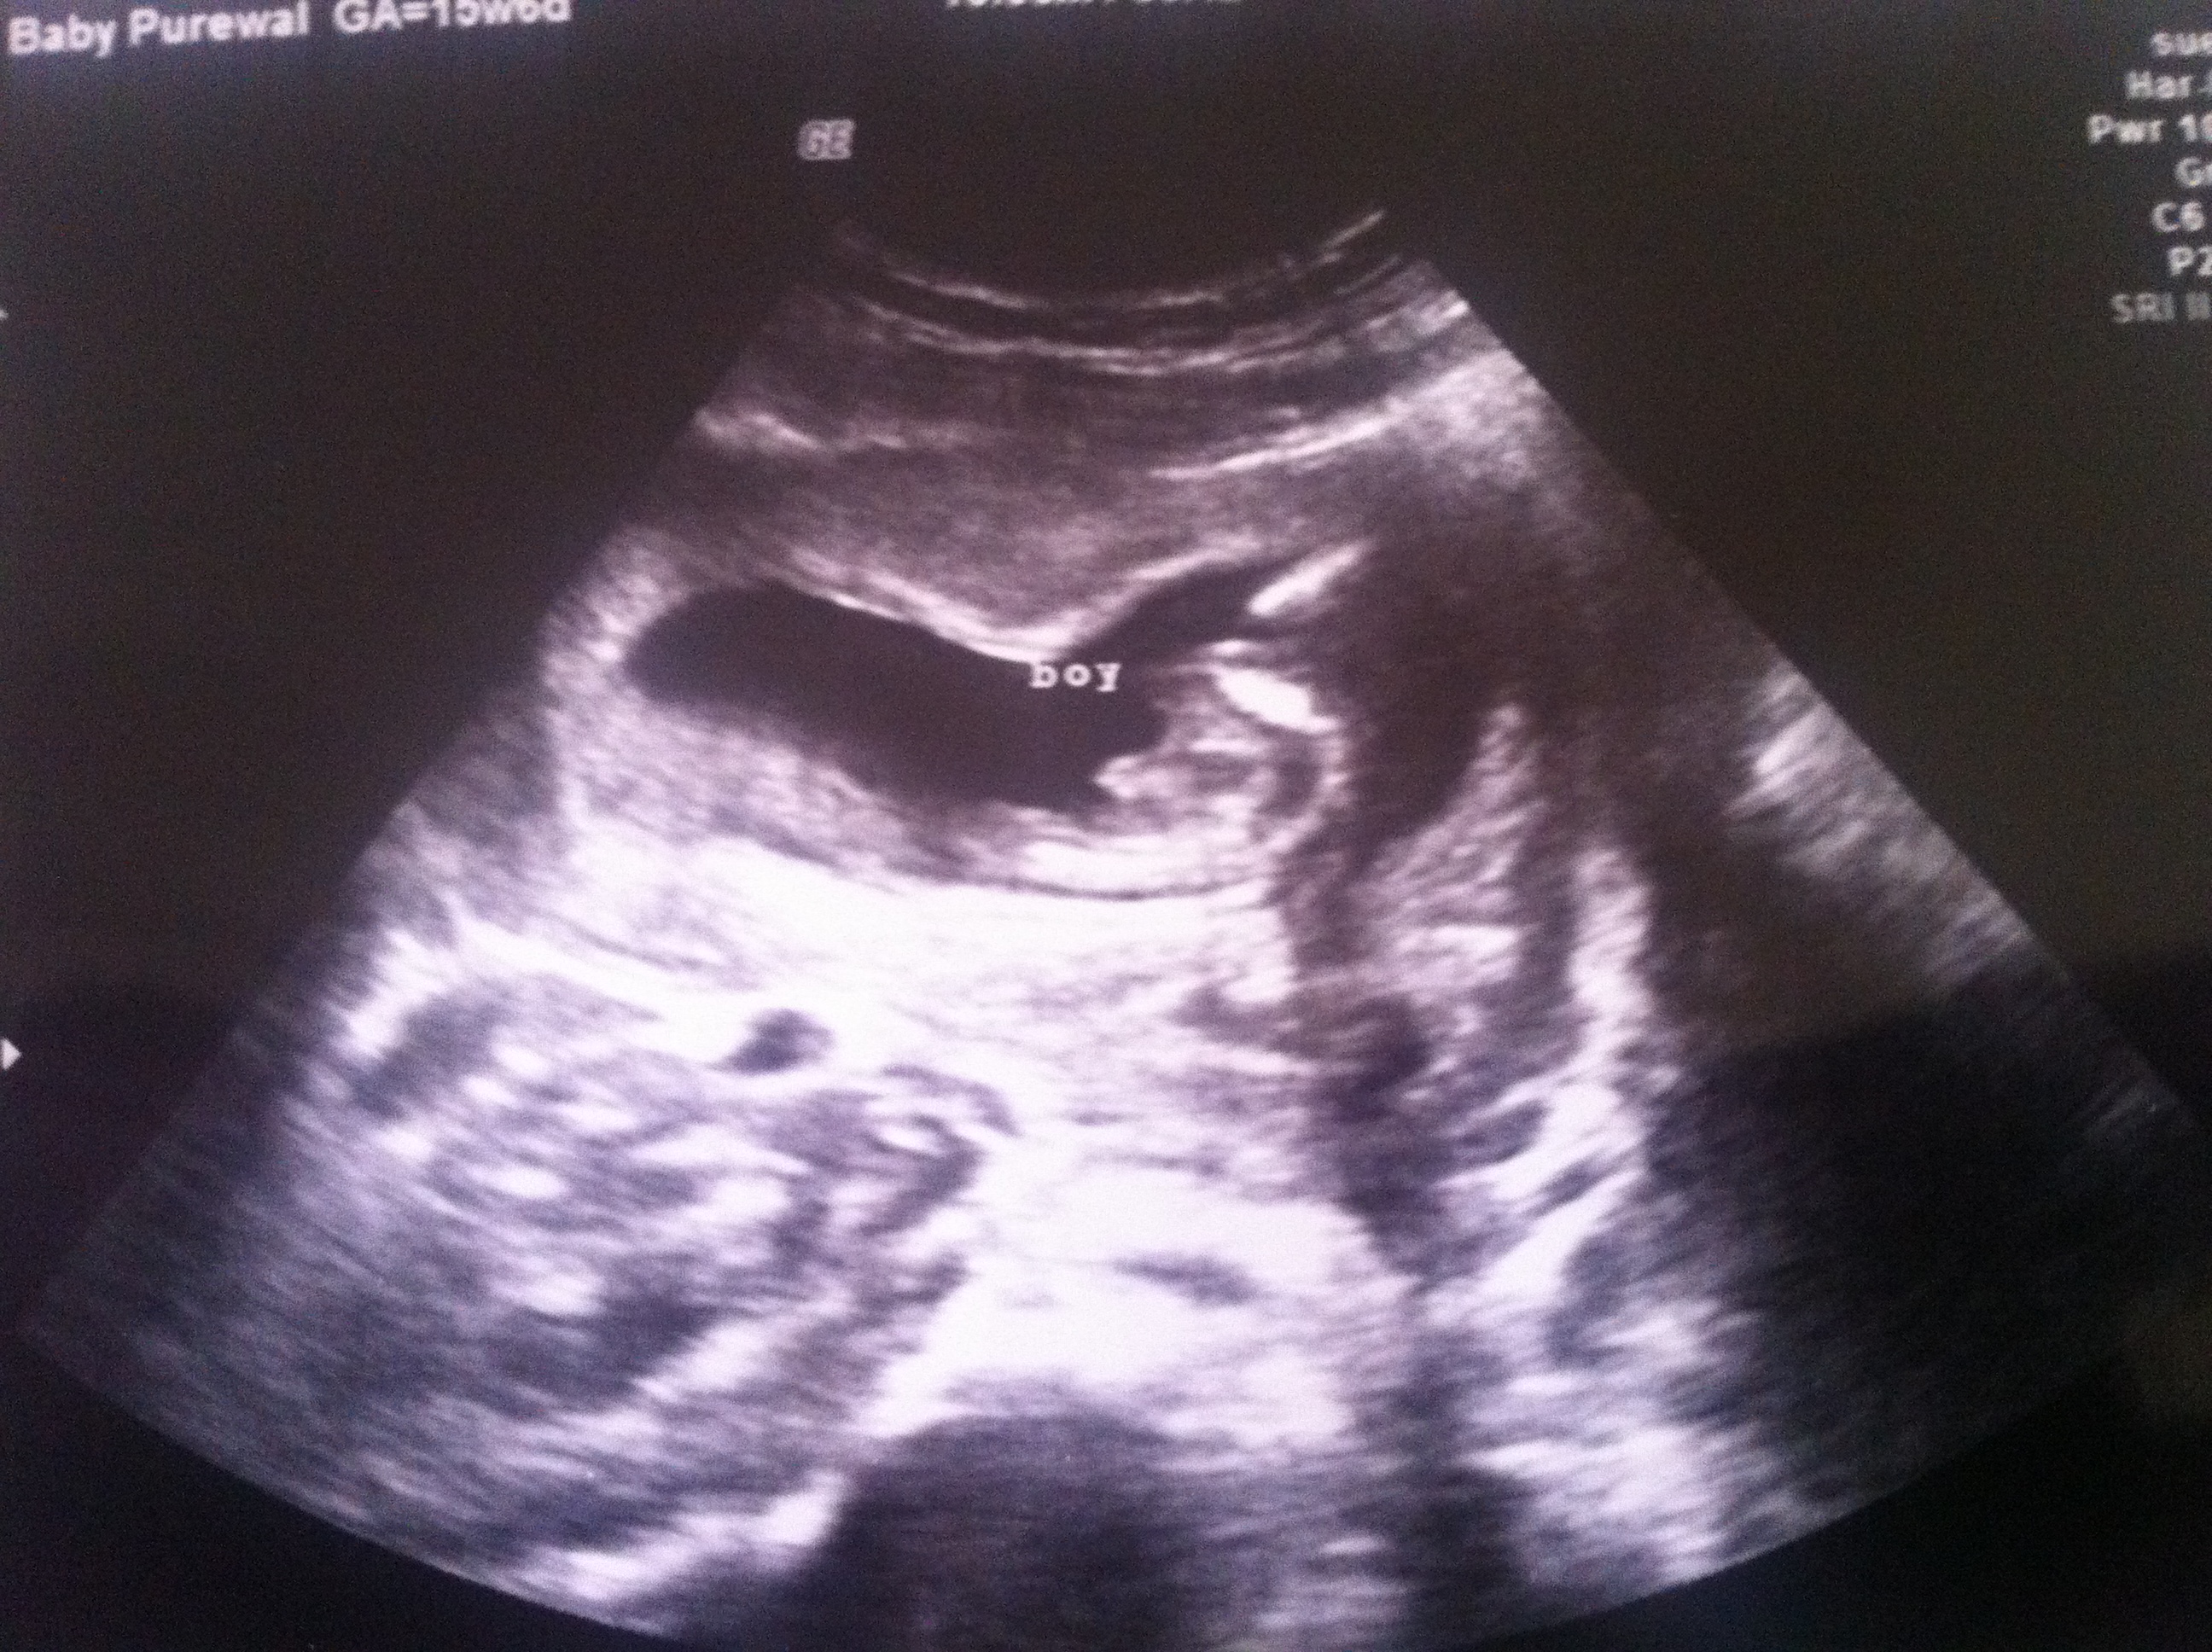

16 weeks potty shot - definitely a boy???

I had my 16 week gender scan done at Babybond in the UK and the tech said she never guesses and is pretty certain that I've got a little baby boy cooking inside me at the moment!

What do you all think? The little winky couldn't be mistaken for a girly nub or completely disappear at this stage could it? I was exactly 16 wks.

Attachment 14454